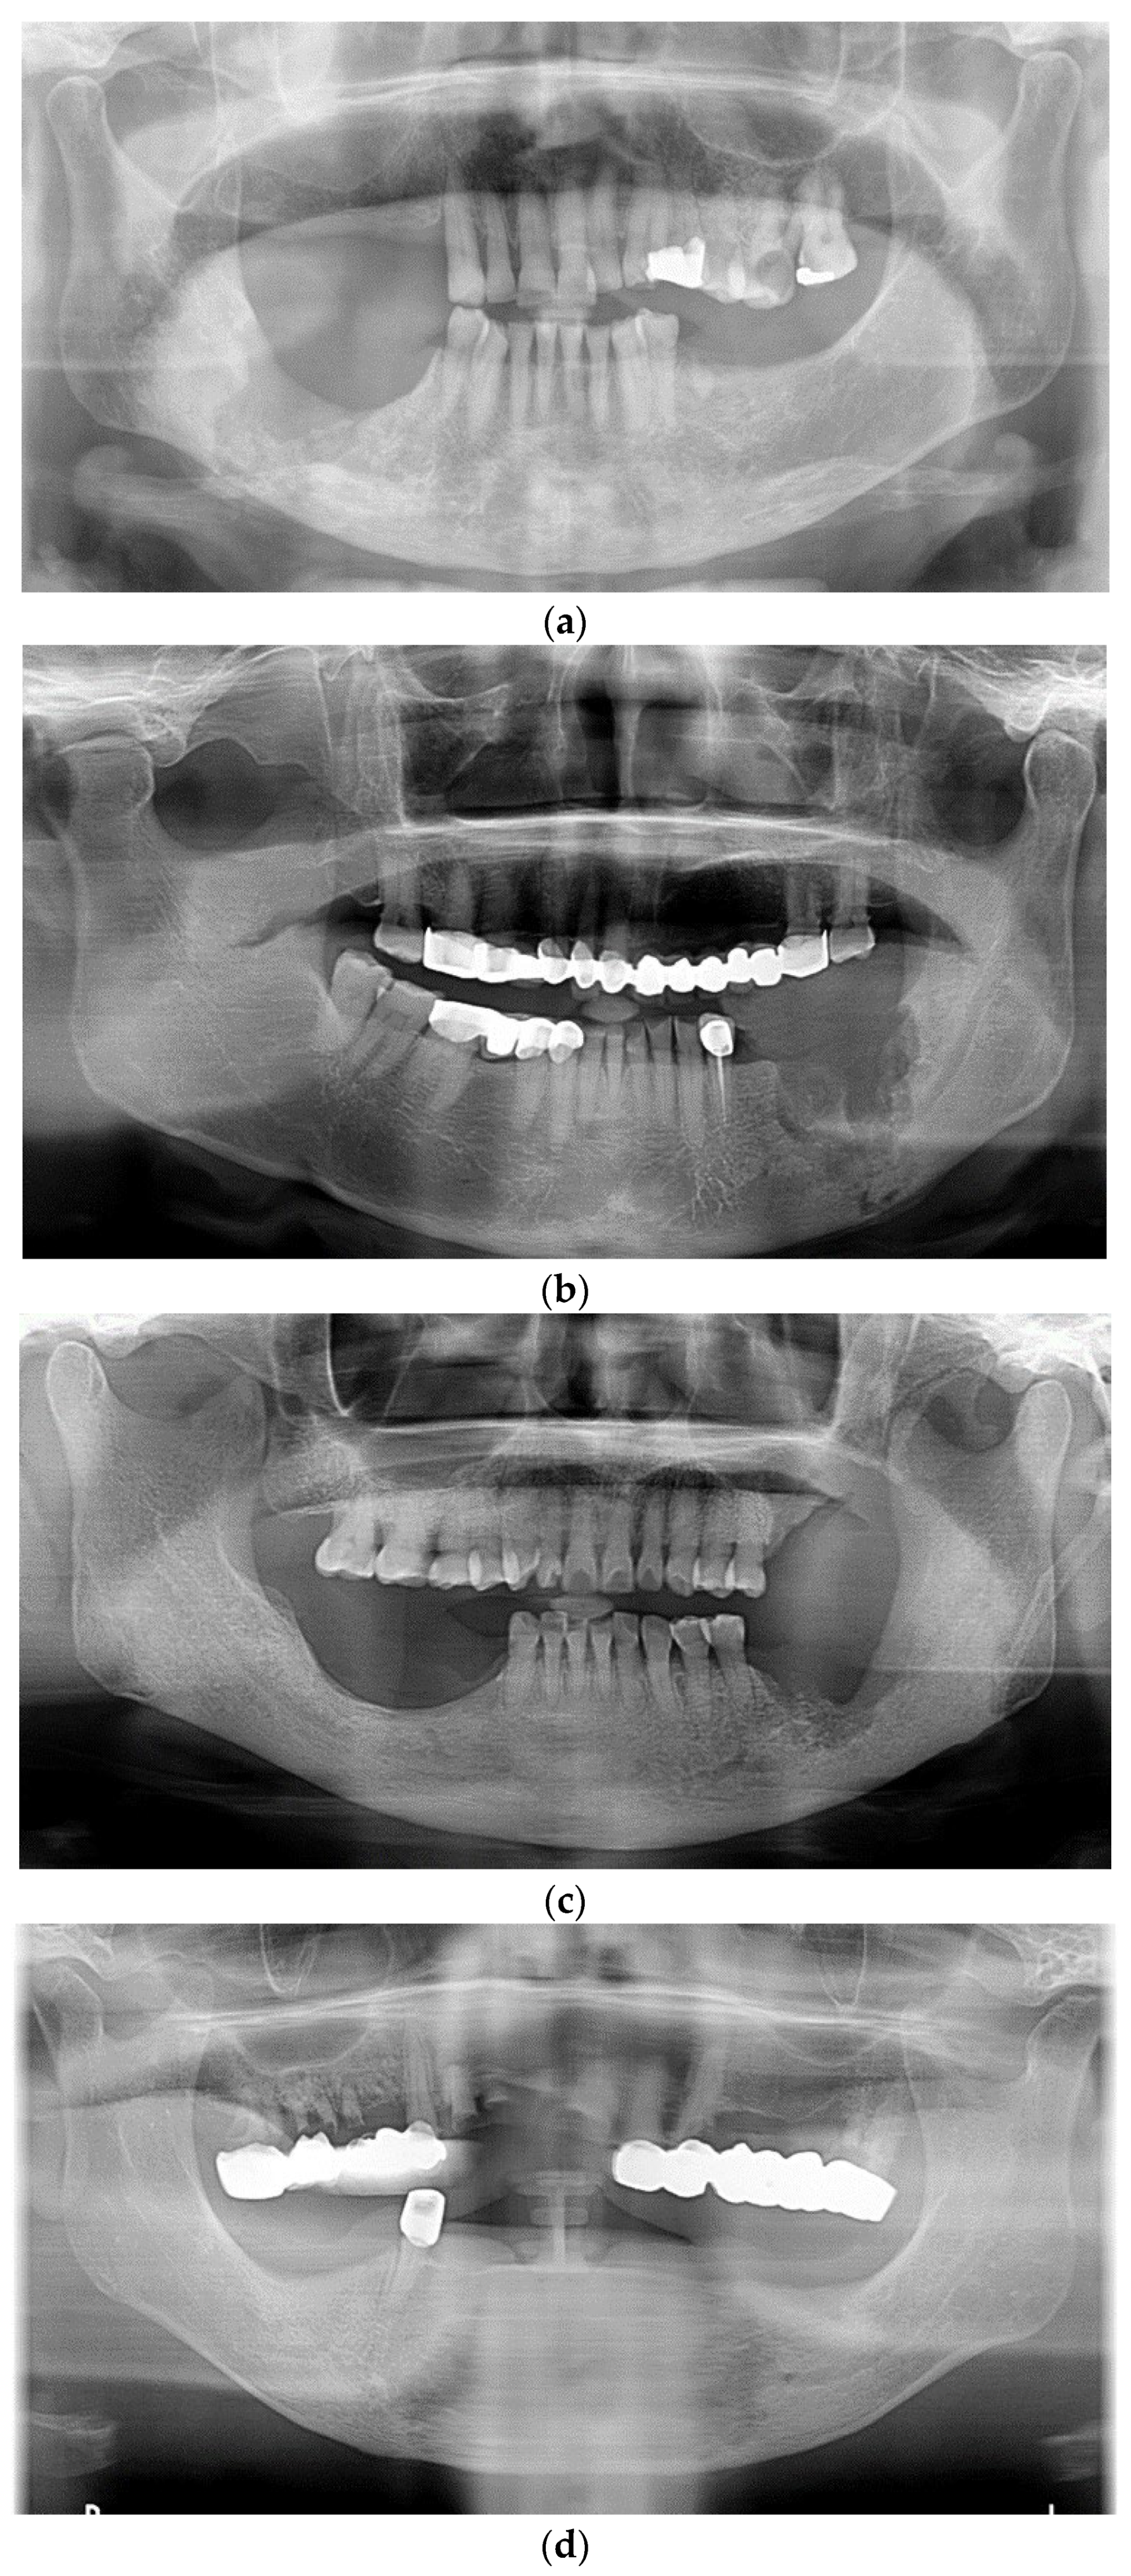

Spontaneous Osteogenic Potential of Periosteum after Segmental Mandibulectomy in Patients with Medication-Related Osteonecrosis of the Jaw (MRONJ): A Retrospective Study of 14 Cases

3. Results